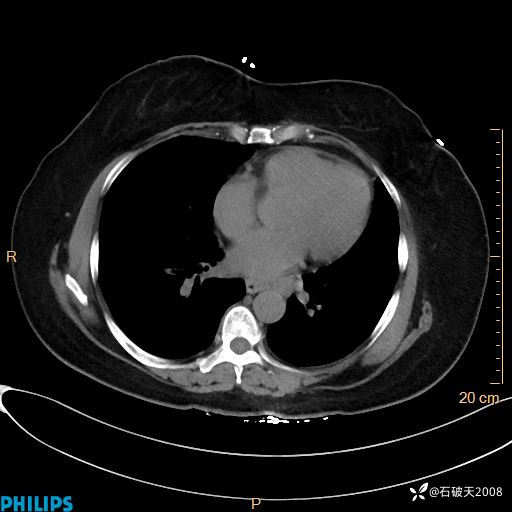

肺结节病?纵膈型肺癌?淋巴瘤?有点意思,欢迎围观

女 52岁 主 诉:咳嗽10余天,咳痰2天。

现病史:10余天前无明显诱因出现咳嗽,呈阵发性干咳,伴咽喉部发痒,无咽痛,无咳痰,无鼻塞、流涕、打喷嚏,无发热、畏寒、寒颤,无头痛、头晕,无胸闷、胸痛,无反酸、烧心,无腹痛、腹泻,无尿频、尿急,无皮疹等,在当地诊所求治,给予口服药物治疗(具体不详),病情无好转。遂在当地社区卫生服务中心开具口服药物治疗(具体不详),疗效欠佳。2天前出现咳痰,在我院门诊求治,行胸部CT提示肺部感染,建议住院,患者要求口服药物治疗,目前仍咳嗽、咳白色粘痰,白天量多,夜间自觉喉部喘鸣音,遂再次来院就诊,以“肺部感染”为诊断收入院。发病以来,神志清,精神可,饮食可,夜间睡眠差,大小便正常,近期体重无明显变化。

肺窗

纵隔窗